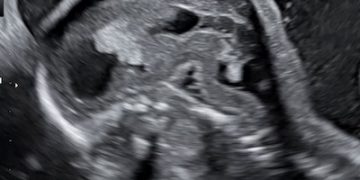

Cari soci, finalmente online le soluzioni dei casi del mese di Luglio Grazie a Carlotta Zorzi e Daniele Di Mascio!! Caso 1 - video [pdf-embedder url="https://www.sieog.it/wp-content/uploads/2024/07/risposta-Casodelmese_Luglio20241.pdf" title="risposta...